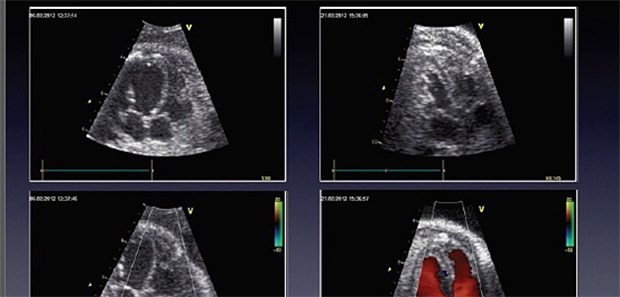

New Yorker Wissenschaftler um Philippe Généreux suchen daher Prädiktoren, mit denen sich Hochrisikopatienten identifizieren lassen, die von einem frühen Klappenersatz profitieren könnten. Als echokardiografische Kriterien haben sie eine linksventrikuläre Ejektionsfraktion <50 Prozent und eine Klappenöffnungsfläche <0,75 cm2 ausgemacht, ebenso wie abnormale Befunde im Stresstest oder ein Anstieg des mittleren Druckgradienten >18 oder 20 mmHg bei einem Belastungs-Stresstest. Der BNP-Wert (Cut-Off: >97 pg/ml)hat sich in einem prospektiven Register mit 70 Patienten als besserer Prädiktor für die Sterblichkeit herausgestellt als die Aortenklappenöffnungsfläche.